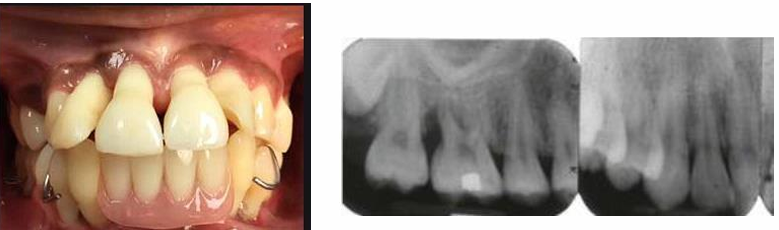

MFD EXAMS /23 6 1234567891011121314151617181920212223 You have 30 min to complete this exam. The timer will start once you begin Attention: Only a few minutes left! Please submit your answers soon. MFD 1 Get a quick sneak peek before the real exam !This trial quiz is designed to show you the question style, difficulty level, and how the options will appear on the platform. 1 / 23 1. What is the lethal dose and toxic dose of fluoride, management? Check 2 / 23 2. What the advantage of silver diamine over other methods and disadvantages ? Check 3 / 23 3. Method of topical fluoride application with concentration ? Check 4 / 23 4. What will happen if left untreated? Check 5 / 23 5. What changes that will happen if the habit stopped? Check 6 / 23 6. Give 3 of your initial stage of treatment? Check 7 / 23 7. What are the causes? Check 8 / 23 8. What is this? Check 9 / 23 9. Then they specified the type of pain and asked about the diagnosis Check 10 / 23 10. What other tests to check vitality of the pulp? Check 11 / 23 11. What are the factors will govern the Rx of Posterior cross bite ? Check 12 / 23 12. What are the factors that govern the treatment of anterior cross bite? Check 13 / 23 13. Name the appliance that you can use to treat this case? Check 14 / 23 14. Name 3 causes? Check 15 / 23 15. Name the most important clinical diagnostic information you need to know. (check RCSI intensive course )? Check 16 / 23 16. What do you see? Check 17 / 23 17. What is your treatment? Check 18 / 23 18. Name the investigations needed? Check 19 / 23 19. causes for gingival enlargement ? Check 20 / 23 20. What is the common side effect of this drug? Check 21 / 23 21. Name the drug that he may take to treat this condition? Check 22 / 23 22. The patient may have what? Check 23 / 23 23. What is this clinical condition? Check /31 2 12345678910111213141516171819202122232425262728293031 You have 30 min to complete this exam. The timer will start once you begin Attention: Only a few minutes left! Please submit your answers soon. MFD 2 Get a quick sneak peek before the real exam !This trial quiz is designed to show you the question style, difficulty level, and how the options will appear on the platform. 1 / 31 1. Mention 2 fixed space maintainers and 2 removable space maintainers other from mentioned : Check 2 / 31 2. Other space maintenance used for child lost primary second molar E before the eruption of the permanent molars ? Check 3 / 31 3. What are the difference between nance appliance and Transpalatal arch Check 4 / 31 4. What material used to attach band? Check 5 / 31 5. What instruction you give to patient? Check 6 / 31 6. Name other fixed space maintainer used in upper jaw and mechanism of their action? Check 7 / 31 7. What component of this appliance? Check 8 / 31 8. What is this appliance , for what its used ? Check 9 / 31 9. Treatment? Check 10 / 31 10. Define Abrasion and Erosion? Check 11 / 31 11. What does this picture show? Check 12 / 31 12. what investigations you can do ? Check 13 / 31 13. Drugs can lead to lichenoid reaction Check 14 / 31 14. What extra oral features in “ Lichenoid reaction )? Check 15 / 31 15. What microscopical features of it ( licheonoid reaction )? Check 16 / 31 16. Definitive diagnosis ? Check 17 / 31 17. Mention type of suggested biopsy ? Check 18 / 31 18. Mention 4 differential diagnosis ? Check 19 / 31 19. Mention 4 questions you will ask the patient ? Check 20 / 31 20. Give 4 intraoral decription of what you see ? Check 21 / 31 21. What the other surgery can be performed to make prothesis? Check 22 / 31 22. Can this tooth stand with fixed prothesis? (in the opg )à taken from Malek file ? Check 23 / 31 23. Radiograph of missing multiple teeth consider it according to Antes law? ON which tooth you will make Abutment ? Check 24 / 31 24. What is Antes law? Check 25 / 31 25. What is best one to use as abutment in fixed prosthesis A or B? Check 26 / 31 26. What relevance of this picture? Check 27 / 31 27. What’s complication of doing surgery in this area floor of mouth? Check 28 / 31 28. Other 2 radiograph needed in diagnosis? Check 29 / 31 29. Give 4 differential diagnosis? Check 30 / 31 30. What can you see ? Check 31 / 31 31. What is the name of radiograph? Check Your score is /30 1 123456789101112131415161718192021222324252627282930 You have 30 min to complete this exam. The timer will start once you begin Attention: Only a few minutes left! Please submit your answers soon. MFD 3 Get a quick sneak peek before the real exam !This trial quiz is designed to show you the question style, difficulty level, and how the options will appear on the platform. 1 / 30 1. Treatment? Check 2 / 30 2. Histopathology? Check 3 / 30 3. Differential diagnosis Check 4 / 30 4. Clinical features’? Check 5 / 30 5. Patient said, this lesion is very frequent, why? Check 6 / 30 6. What are the causes for ulcers? Check 7 / 30 7. Patient have other signs like uveitis ,Genital ulcerations which syndrome he had ? Check 8 / 30 8. Name of the lesion ? Check 9 / 30 9. Mention some TMJ movement ? Check 10 / 30 10. Blood supply ? Check 11 / 30 11. Nerve supply ? Check 12 / 30 12. Which muscles close? Check 13 / 30 13. Action of open and open wide? Check 14 / 30 14. Why it’s Atypical joint ? Check 15 / 30 15. Name of the ligaments ? Check 16 / 30 16. What would be your management? Check 17 / 30 17. Bacteria involved Check 18 / 30 18. Which type of Periodontitis? Check 19 / 30 19. Treatment? Check 20 / 30 20. Histopathology? Check 21 / 30 21. Differential diagnosis? Check 22 / 30 22. Clinical features? Check 23 / 30 23. What are the time frames for making a complaint? Check 24 / 30 24. What are the 3 points related to negligence? Check 25 / 30 25. Who is allowed access to the patient records? Check 26 / 30 26. How to differentiate if it is upper or lower motor neuron lesion? Check 27 / 30 27. Management? Check 28 / 30 28. What are the causes? Check 29 / 30 29. What should you advise the patient to do? Check 30 / 30 30. What is this lesion? Check Your score is /24 1 123456789101112131415161718192021222324 You have 30 min to complete this exam. The timer will start once you begin Attention: Only a few minutes left! Please submit your answers soon. MFD 4 Get a quick sneak peek before the real exam !This trial quiz is designed to show you the question style, difficulty level, and how the options will appear on the platform. 1 / 24 1. What does MRONJ stands for? Check 2 / 24 2. Give definition for MRONJ Check 3 / 24 3. For what medical problems these medications are used? Check 4 / 24 4. Stages of MRONJ 3 Check 5 / 24 5. What’s this appliance? Check 6 / 24 6. At what age is it used? Check 7 / 24 7. What type of malocclusion is it used to treat? Check 8 / 24 8. What changes will produce? (4 options) Check 9 / 24 9. Disadvantages? Check 10 / 24 10. Why is it flabby tissue? Check 11 / 24 11. what is this condition called? Check 12 / 24 12. Causes ? Check 13 / 24 13. Clinical Features ? Check 14 / 24 14. How to avoid it ? Check 15 / 24 15. Management? Check 16 / 24 16. Ideal post length and width Check 17 / 24 17. Definition of Ferrule it’s the Check 18 / 24 18. What is the importance of the ferrule effect ? Check 19 / 24 19. Describe the radiolucency? Check 20 / 24 20. Give 6 differential diagnosis? Check 21 / 24 21. Give 5 radiographical features? Check 22 / 24 22. What is the difference between incisional and excisional biopsy? Check 23 / 24 23. What other 2 plain radiographs we can we can take? Check 24 / 24 24. ALARA? Check Your score is /22 1 12345678910111213141516171819202122 You have 30 min to complete this exam. The timer will start once you begin Attention: Only a few minutes left! Please submit your answers soon. MFD 5 Get a quick sneak peek before the real exam !This trial quiz is designed to show you the question style, difficulty level, and how the options will appear on the platform. 1 / 22 1. . Types of external root resorption? Check 2 / 22 2. The cause of root resorption in the pic? Check 3 / 22 3. How you will treat it? Check 4 / 22 4. What is this probe? Check 5 / 22 5. What is the mark a ? Check 6 / 22 6. What is the mark b ? Check 7 / 22 7. What is the score from the given reading? Check 8 / 22 8. What is the treatment need of the patient according to the score? Check 9 / 22 9. What is the differential diagnosis ? Check 10 / 22 10. Four clinical features of the lesion? Check 11 / 22 11. Treatment ? Check 12 / 22 12. Describe what do you see? Check 13 / 22 13. Causes for it ? Check 14 / 22 14. Treatment ? Check 15 / 22 15. Picture of patient with Anaphylaxis…after taking Check 16 / 22 16. What is diagnosis? - Check 17 / 22 17. What a the signs of Anaphyalxis reactions ? Check 18 / 22 18. What first line of treatment? Dose? Route of Adminstration? Check 19 / 22 19. Other drug used? Check 20 / 22 20. What are expected complications if not treated ? Check 21 / 22 21. What precautions should be made to prevent anaphylaxis reaction ? - Check 22 / 22 22. Name 10 drug in emergency used with their route of Administration and their condition they use in? Check Your score is /36 1 123456789101112131415161718192021222324252627282930313233343536 You have 30 min to complete this exam. The timer will start once you begin Attention: Only a few minutes left! Please submit your answers soon. MFD 6 Get a quick sneak peek before the real exam !This trial quiz is designed to show you the question style, difficulty level, and how the options will appear on the platform. 1 / 36 1. . What are cases that you have to extract the primary tooth? Check 2 / 36 2. D. What are the indications for extraction? Check 3 / 36 3. What are your treatment options? Check 4 / 36 4. Investigations? Check 5 / 36 5. Type of trauma? Check 6 / 36 6. Patient diagnosed with sjorgen syndrome Histology ? - Check 7 / 36 7. Patient diagnosed with sjorgen syndrome Mention four blood investigations ? Check 8 / 36 8. Patient diagnosed with sjorgen syndrome Mention two sites where can we take the biopsy Check 9 / 36 9. Patient diagnosed with sjorgen syndrome How can you differentiate between primary and secondary ? Check 10 / 36 10. Gingival inflammation present in which syndrome Check 11 / 36 11. What is the treatment? Check 12 / 36 12. mention another connective tissue disease that can lead to lesions “ intraorally “ similar to the Lichen planus ? Check 13 / 36 13. what serious complication can arise from Erosive lichen planus ? Check 14 / 36 14. If it was atrophic lesion what histology might be seen ? Check 15 / 36 15. List the histological features of lichen planus ? Check 16 / 36 16. Lichen planus what dose it affect? Check 17 / 36 17. Age group commonly affected ? -ref SAQ Check 18 / 36 18. What are the clinical presentation ‘ types of lichen planus ‘ Check 19 / 36 19. What might you see in patient’s body that has a relation to this lesion? Check 20 / 36 20. What are the differential diagnoses? Check 21 / 36 21. Factors for platelet adhesion? Check 22 / 36 22. What can you see? Check 23 / 36 23. Other 2 process of hemostasis? Check 24 / 36 24. Two diseases in which they increase ? Check 25 / 36 25. Two diseases in which they decrease? Check 26 / 36 26. Medical term when they decrease? And if they increased Check 27 / 36 27. Function Check 28 / 36 28. Life span ? Check 29 / 36 29. From where they arise? Check 30 / 36 30. Normal number? Check 31 / 36 31. What are the function of the guiding plane ? Check 32 / 36 32. The success rate ? Check 33 / 36 33. Mention single extra preparation requirement for Resin bonded bridge in posterior teeth ? Check 34 / 36 34. Mention 5 preparation features of it? Check 35 / 36 35. Give two advantages of it ? Check 36 / 36 36. What’s the name of this prosthesis? Check Your score is /23 1 1234567891011121314151617181920212223 You have 30 min to complete this exam. The timer will start once you begin Attention: Only a few minutes left! Please submit your answers soon. MFD 7 Get a quick sneak peek before the real exam !This trial quiz is designed to show you the question style, difficulty level, and how the options will appear on the platform. 1 / 23 1. If the same scenario but the tooth is subluxated. What is the management? Check 2 / 23 2. Aim of this procedure Check 3 / 23 3. Steps to do this procedure? Check 4 / 23 4. Management? How to asses the vitality of the tooth Check 5 / 23 5. Mention factors that can affect the treatment plan ? Check 6 / 23 6. Identify the Kenneyd’s classification Check 7 / 23 7. Name its parts? Check 8 / 23 8. Uses of Surveyor Check 9 / 23 9. What is this ? Check 10 / 23 10. Criteria for hand piece sterilization Check 11 / 23 11. steps for wrapped instrument sterilization process ( ref : sterilization in SDCEP)? Check 12 / 23 12. What is the difference between sterilization and decontamination? Check 13 / 23 13. Optimal temperature & pressure & time for autoclave? Check 14 / 23 14. Difference between vacuum and non-vacuum autoclave in mechanism? Check 15 / 23 15. Optimum temperature? Check 16 / 23 16. Advantage of vaccum over non vaccum? Check 17 / 23 17. What is the significance of forehead wrinkling? Check 18 / 23 18. What is Ramsy haunt syndrome ? Rx ? and is it LMN or UMN ? Check 19 / 23 19. Enumerate 3 extracranial and intracranial causes for this ? Check 20 / 23 20. What are the branches of facial nerve? Check 21 / 23 21. Why do we suture the eye in a patient with Facial Palsy? Check 22 / 23 22. Differentiate between Upper and Lower Motor Neuron lesions? Check 23 / 23 23. What is shown in photograph? Check Your score is /27 0 123456789101112131415161718192021222324252627 You have 30 min to complete this exam. The timer will start once you begin Attention: Only a few minutes left! Please submit your answers soon. MFD 8 Get a quick sneak peek before the real exam !This trial quiz is designed to show you the question style, difficulty level, and how the options will appear on the platform. 1 / 27 1. Mention 4 diseases you would see in HIV Patients? Check 2 / 27 2. Give 2 differential diagnosis for this lesion? Check 3 / 27 3. Describe the lesion shown in Photograph B? Check 4 / 27 4. What is your diagnosis ? Check 5 / 27 5. Describe the lesion shown in Photograph A? Check 6 / 27 6. Disadvantages of gold ? Check 7 / 27 7. Ideal cement for All Porcelain? Check 8 / 27 8. Which cement would u use for high caries risk patient? Check 9 / 27 9. How much would you prepare for functional and non-functional cusps in Gold Crown? Check 10 / 27 10. what crown would you go for in bruxism patients out of these 3? Check 11 / 27 11. Name the 3 restorations? Check 12 / 27 12. After administering Local Anesthesia and deciding the choice of biopsy. What should be done before biopsying the lesion? Check 13 / 27 13. Name 2 systemic steroids with dosage you would recommend for this patient? Check 14 / 27 14. Name 2 topical steroids with dosage you would recommend for this patient? Check 15 / 27 15. What is your diagnosis? Check 16 / 27 16. Describe the lesion shown in photograph? Check 17 / 27 17. Name 5 options to increase retention and stability in class l Check 18 / 27 18. E. What is the function of the RPI system ? Check 19 / 27 19. What are the 2 disadvantages of the 2 restorations you mentioned? Check 20 / 27 20. What materials are your 2 restorations made of? Check 21 / 27 21. Other than implants what restoration would you place in this patient? Check 22 / 27 22. Which Kennedy’s classification is this? Check 23 / 27 23. Describe your management? Check 24 / 27 24. What may be the patient complaint? Check 25 / 27 25. What are the causes of this? Check 26 / 27 26. Describe what you see in the photograph? Check 27 / 27 27. which 4 examinations would you undertake? Check Your score is /31 0 12345678910111213141516171819202122232425262728293031 You have 30 min to complete this exam. The timer will start once you begin Attention: Only a few minutes left! Please submit your answers soon. MFD 9 Get a quick sneak peek before the real exam !This trial quiz is designed to show you the question style, difficulty level, and how the options will appear on the platform. 1 / 31 1. Describe what you see in the photograph? Check 2 / 31 2. Three other features of this syndrome ? Check 3 / 31 3. What is the medical condition associated with it “? Multiple OKC? Check 4 / 31 4. Where expansion occurs in the OKC ? Check 5 / 31 5. From which cells this lesion arises from? Check 6 / 31 6. What is your diagnosis? Check 7 / 31 7. What is the histopathology of the lesion shown in Histology slide? Check 8 / 31 8. Give 4 differential diagnosis? Check 9 / 31 9. What is the consequence of premature loss of deciduous teeth? Check 10 / 31 10. Identify those appliances and mention one use for each and mode of action? Check 11 / 31 11. What component of appliance no. 3 ? Check 12 / 31 12. How to overcome open bite disadvantage ? Check 13 / 31 13. What are Disadvantages of this appliance ? Check 14 / 31 14. What Ceph changes are expected while using this appliance ? Check 15 / 31 15. What is the construction of Twin Block Appliance? Check 16 / 31 16. What skeletal and dental changes are expected while using this appliance ? Check 17 / 31 17. What is the ideal age to treat this condition >? Check 18 / 31 18. Indications of the Twin Block Appliance? Two Check 19 / 31 19. Name the Appliance used to correct this? Check 20 / 31 20. What is the treatment? Check 21 / 31 21. How to prevent it Check 22 / 31 22. Mention three mechanisms of action of Fluoride? Check 23 / 31 23. What is the disease caused by excess Fluoride? Check 24 / 31 24. What are the risk factors associated with this patient? Check 25 / 31 25. Name the principal organism causing this? Check 26 / 31 26. what are the principles of the access cavity Check 27 / 31 27. What is your diagnosis? Check 28 / 31 28. What are principles of cavity preparation? Check 29 / 31 29. What is your Periapical diagnosis? Check 30 / 31 30. What is your Pulpal diagnosis? Check 31 / 31 31. Which test would you undertake? Check Your score is /21 0 123456789101112131415161718192021 You have 30 min to complete this exam. The timer will start once you begin Attention: Only a few minutes left! Please submit your answers soon. MFD 10 Get a quick sneak peek before the real exam !This trial quiz is designed to show you the question style, difficulty level, and how the options will appear on the platform. 1 / 21 1. Patient is 20 years old Mention two treatment options for this case ? Check 2 / 21 2. Patient is 20 years old What is the long term risk for not treating this case ? Check 3 / 21 3. Name of this appliance in the next picture? Check 4 / 21 4. What is the wire used ? Check 5 / 21 5. For which orthodontic cases this appliance is necessary ? Check 6 / 21 6. Why we use retainer ? Check 7 / 21 7. Describe what you see ? Check 8 / 21 8. Differential diagnosis:- Check 9 / 21 9. Name of those muscles ? Check 10 / 21 10. Name the Extrinsic muscles of the tongue? Check 11 / 21 11. . Which nerves innervate the Extrinsic muscles of the tongue?. Check 12 / 21 12. What is the somatic innervation of anterior 2/3 of tongue? Check 13 / 21 13. Which nerve supplies the posterior 1/3 of tongue?. Check 14 / 21 14. From which Pharyngeal arch posterior 1/3 derived from? Check 15 / 21 15. Mention the intrinsic muscle of the tongue ? Check 16 / 21 16. What is the name of this condition ? name the lesion on the skin ? Check 17 / 21 17. Mention 3 drugs that causing it ? Check 18 / 21 18. 2 infections associated with it Check 19 / 21 19. Mention 2 immediate treatment ? Check 20 / 21 20. Why this condition can be fatal ? Check 21 / 21 21. Which test would you undertake? Check Your score is